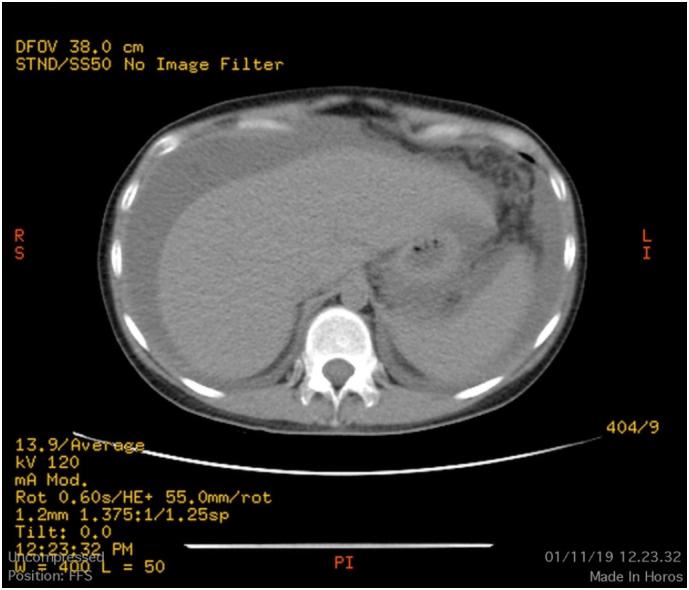

A 36 years-old woman got referred with abdominal distention and weight loss from an internist and digestive surgeon. The abdominal computed tomography said thickening of the stomach wall with ascites. Ultrasound concluded the uterus, ovary, and endometrium within normal. The CA 125 levels elevated to 1200 U/mL and the complete blood count was normal. We were making diagnosis of peritoneal tuberculosis, peritoneal carcinomatosis, and advanced ovarian cancer. We did the diagnostic laparoscopic and taking a biopsy sample, ascites with peritoneal carcinomatosis and omental cake were found, the peritoneal cavity was covered by miliary nodules. Histopathology results concluded peritoneal tuberculosis without malignancy signs. The patient was treated with tuberculosis drugs. The follow-up evaluations show significant clinical improvement.

一名36岁女性因腹胀和体重减轻被内科医生和消化外科医生转诊。腹部计算机断层扫描显示胃壁增厚并伴有腹水。超声检查显示子宫、卵巢和子宫内膜正常。CA 125水平升至1200 U/mL,全血细胞计数正常。我们考虑诊断为腹膜结核、腹膜癌和晚期卵巢癌。我们进行了诊断性腹腔镜检查并取活检样本,发现有腹膜癌和网膜饼状增厚,腹膜腔布满粟粒样结节。组织病理学结果显示为腹膜结核,无恶性迹象。患者接受了抗结核药物治疗。随访评估显示临床症状有显著改善。